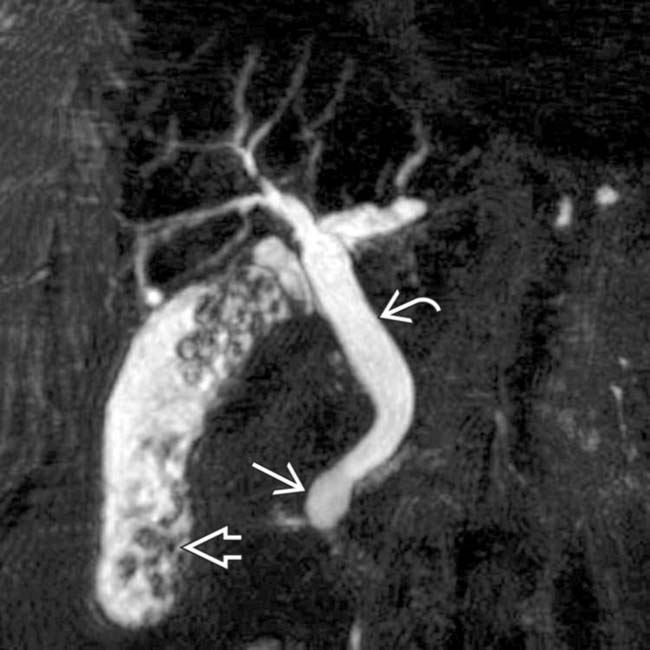

From www.researchgate.net

MRCP showing a type Ic choledochal cyst with a dilated pancreatic duct Type Ic Choledochal Cyst Characterized by fusiform dilation of the extrahepatic bile duct. Biliary cysts, also termed choledochal malformations, are cystic dilations that may occur singly or in multiples throughout. Choledochal cyst is a congenital cystic dilation of a part of bile duct that occurs most commonly in the main part of common. Type i cysts are a dilatation of the extrahepatic bile duct.. Type Ic Choledochal Cyst.